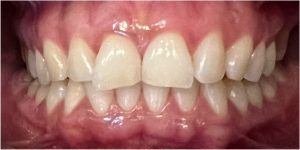

Pod kierownictwem lek. stom. Michała Badowskiego po wnikliwej analizie została przeprowadzona korekta dziąseł i pozbycie się nieestetycznych koron na podbudowie metalowej, eliminując tym samym nawracające stany zapalne dziąseł.

Następnie została wykonana wizualizacja nowego uśmiechu, idealnie dopasowana do twarzy Pacjentki. Po jej akceptacji, przygotowaliśmy komplet koron i licówek pełnoceramicznych na górne i dolne zęby.

Całe leczenie trwało zaledwie 3 miesiące!

Dzięki współpracy lek. stom. Michała Badowskiego i techn. dent. Joanny Gancarz z laboratorium Dentalscan Pacjentka zachwyca pięknym uśmiechem!